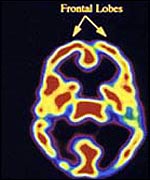

The scans provided remarkable clues about what goes on in the brain during meditation.

"There was an increase in activity in the front part of the brain, the area that is activated when anyone focuses attention on a particular task," Dr Newberg explained.

In addition, a notable decrease in activity in the back part of the brain, or parietal lobe, recognised as the area responsible for orientation, reinforced the general suggestion that meditation leads to a lack of spatial awareness.

Dr Newberg explained: "During meditation, people have a loss of the sense of self and frequently experience a sense of no space and time and that was exactly what we saw."